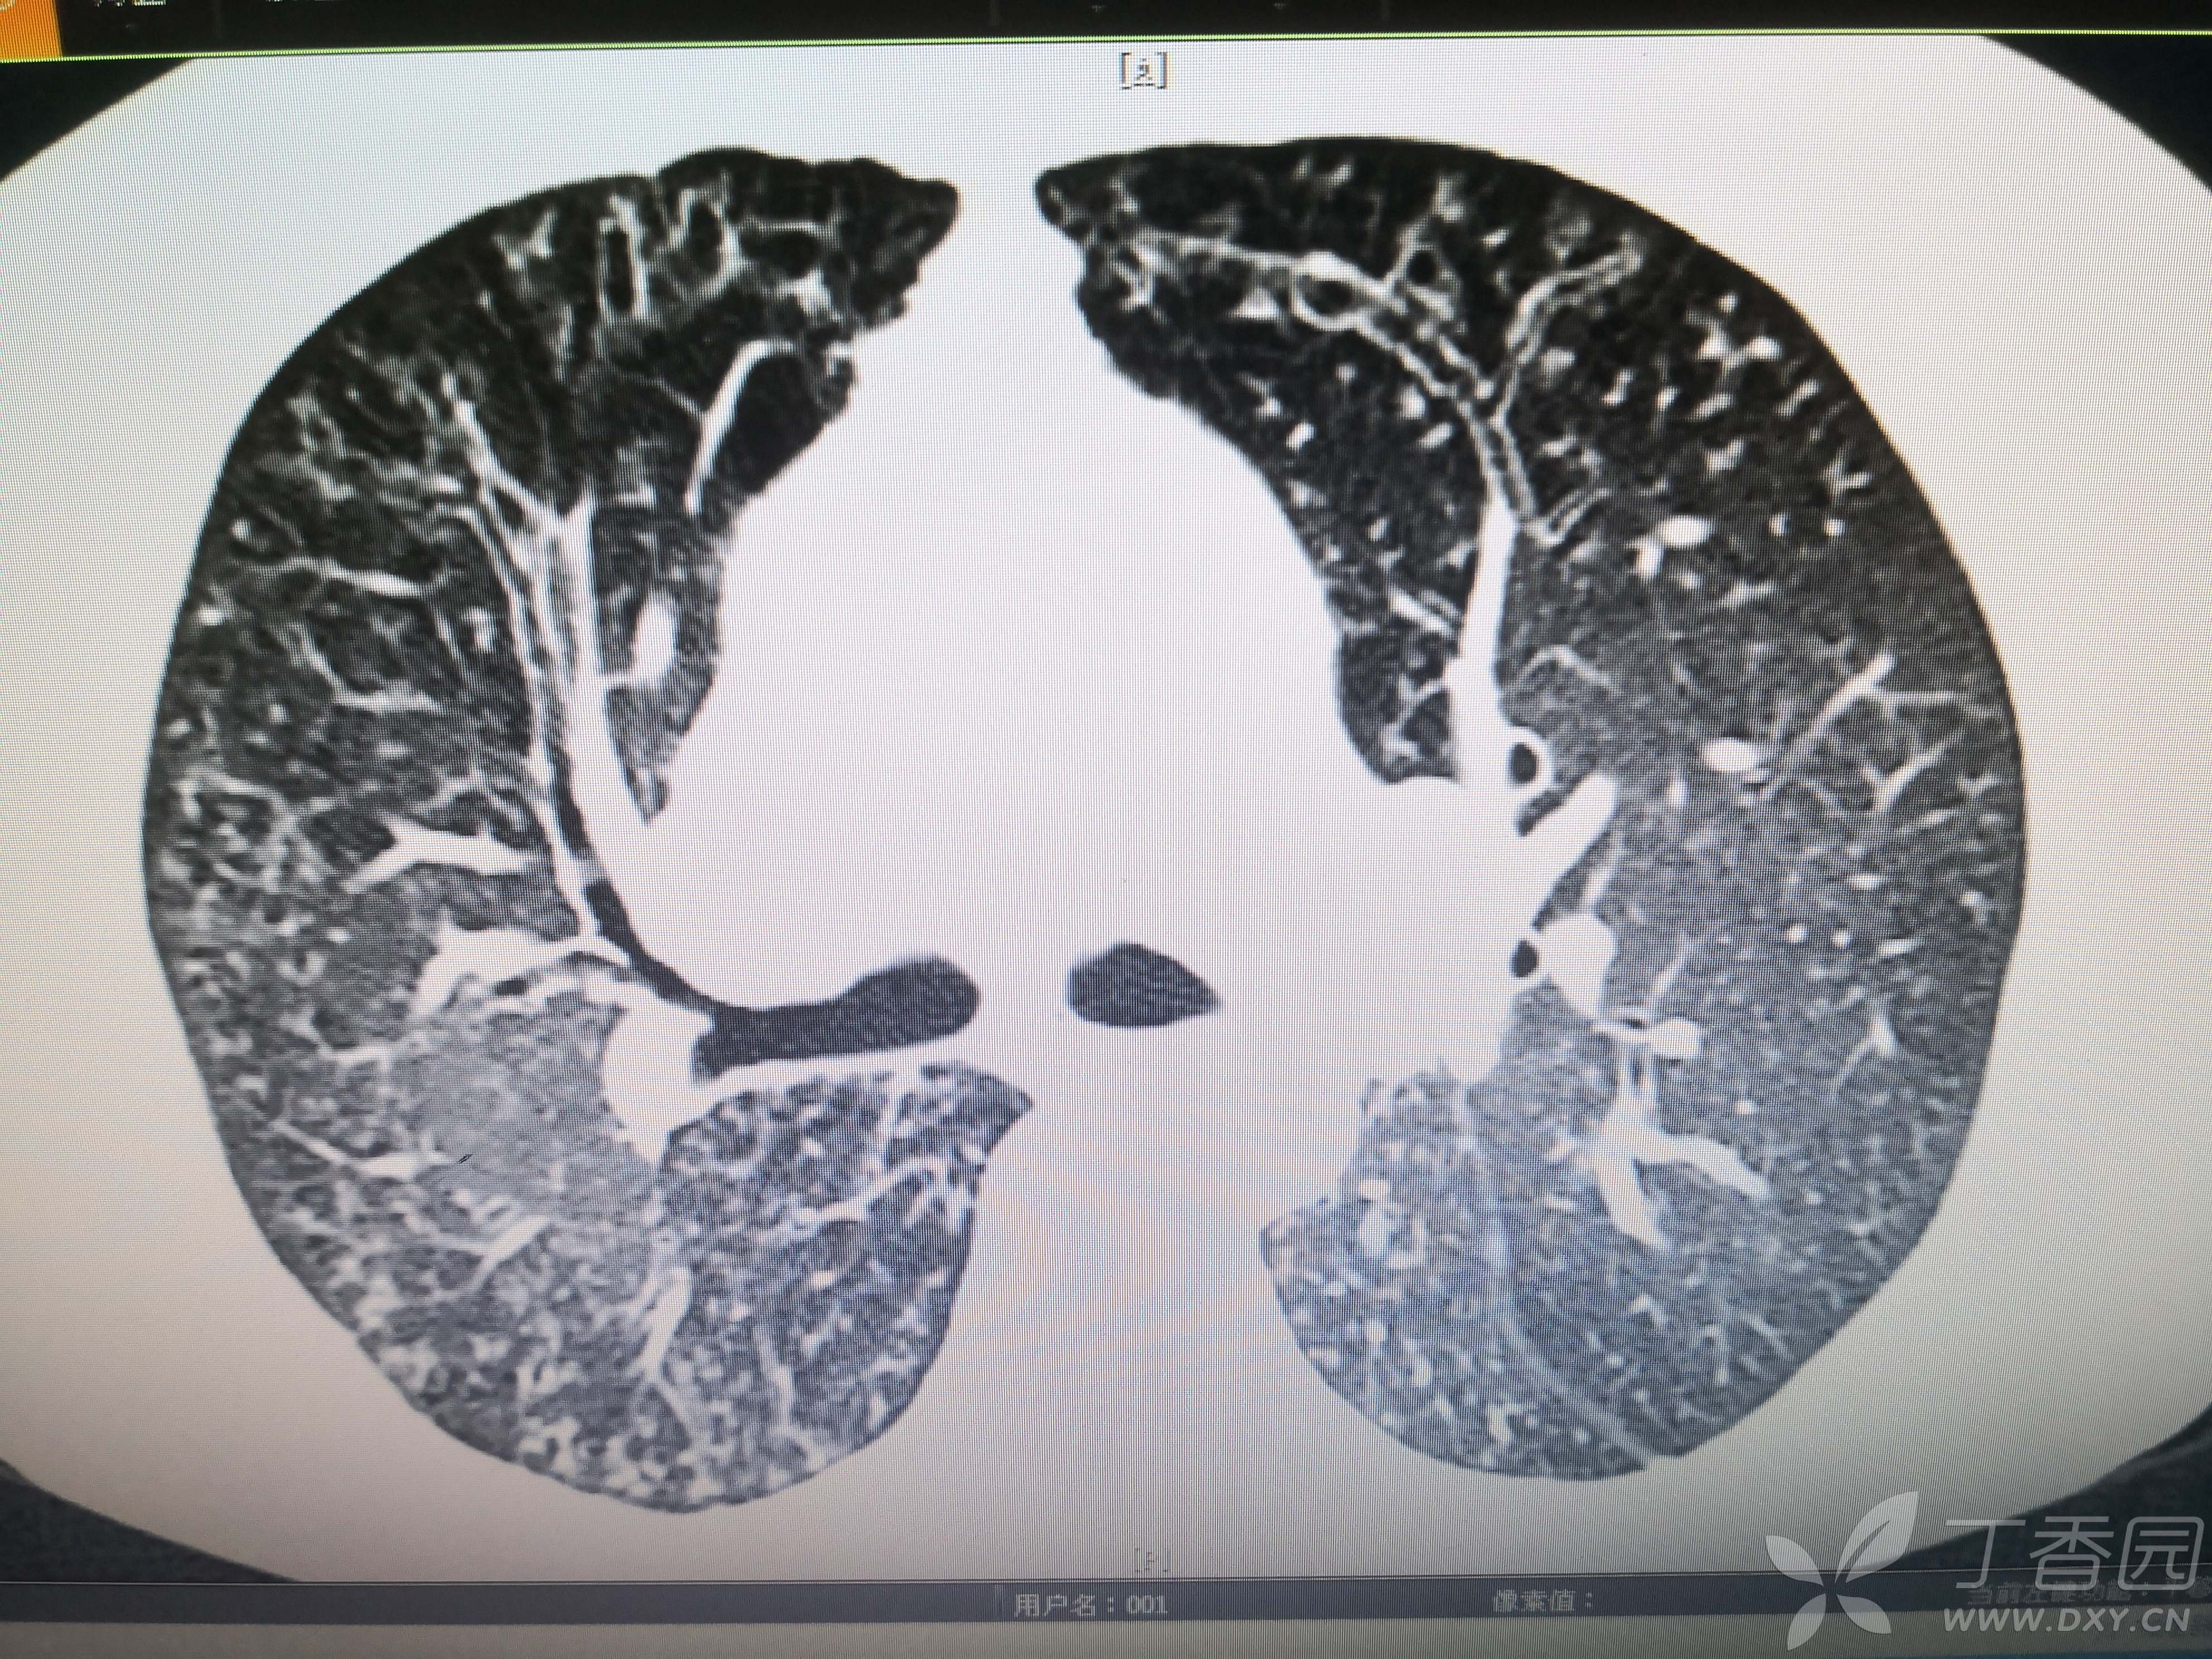

患者性别:女

患者年龄:54岁

简要病史:反复咳嗽、咳脓痰40余年,气喘10年,加剧2周。

体格检查:SpO2:72%,双中下肺闻及中小湿啰音。

辅助检查:见图

临床诊断:支气管扩张并感染

治疗经过:哌拉西林他坐巴坦联合左氧氟沙星抗感染